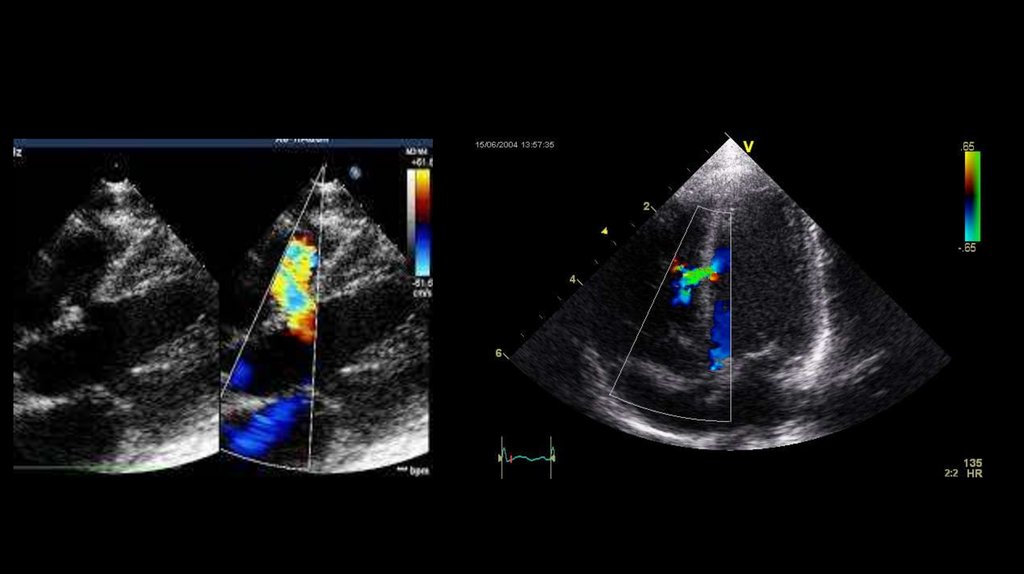

13. ЭхоКГ открытого артериального протока

14.